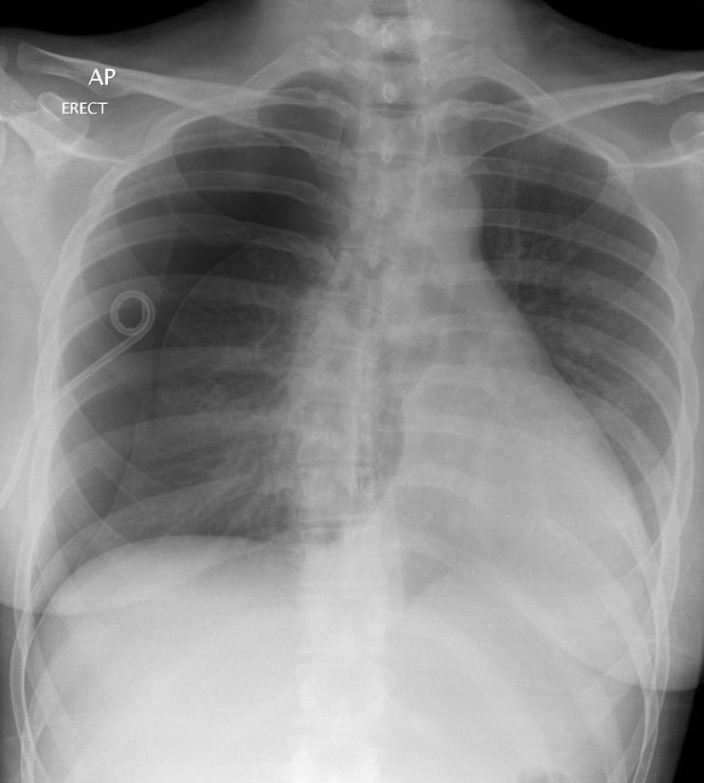

25-year-old female with no background available

Radiolucent area in right lung field with compressive atelectasis of right lung and mediastinal shift to the left consistent with pneumothorax